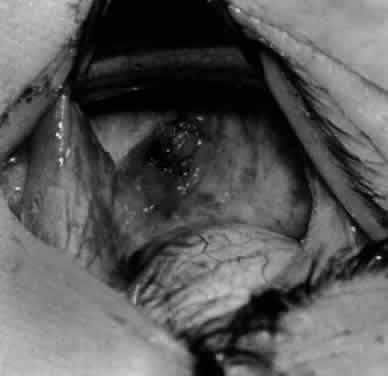

Fig. 24. The eyelid speculum is removed and a Desmarres lid retractor is placed inferiorly. The inferior oblique muscle is drawn superiorly and nasally. The fusiform expansion of the inferior oblique muscle is evident on the posterior border, where the nerve to the inferior oblique muscle and artery and vein enter the inferior oblique muscle. The Stevens muscle hook is used to hook the neurovascular bundle.

Fig. 25. The hook is advanced further for identification of the neurovascular bundle on the inferior oblique muscle.